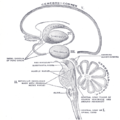

| رسم توضيحي لمسار ألياف lemniscus; medial lemniscus بالأزرق, lateral بالأحمر. | ||

المهاد Thalamus (من اليونانية θάλαμος = المهد أو المخدع, غرفة) هو زوج وجزء متماثل في المخ. وتشكل الجزء الرئيسي من diencephalon.

تعتبر الوظيفة الأساسية لمنطقة المهاد هي الإحساس و يتحكم في الحركة البدنية، و يعتبر كمحطة للإشارات الحسية التي تصل إلى قشرة المخ و يعمل كمركز لتفسير بعض منها، مثل الألم و الشعور بالحرارة و الضغط واللمس. [1]